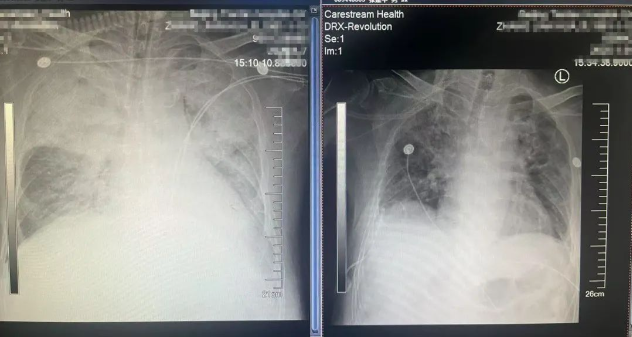

然而,还不等救治团队松一口气,又一个危机接踵而至:张先生突然出现发热、痰多的症状,感染指标持续攀升,CT显示,他的双肺实变(因为种种原因导致肺内正常空气含量消失,变成“实”体)合并胸腔积液,氧合指数(肺脏将吸入的氧气转化为动脉血中氧气的能力,正常值为400-500mmhg)一度降到65mmhg,随时会出现生命危险。检验结果显示,张先生感染了一种名叫“铜绿假单胞菌”的细菌。这种细菌对碳青霉烯类、头孢、喹诺酮类等重要抗生素均耐药,因此也被称为“超级耐药细菌”。

呼吸与危重症医学科团队把张先生转到呼吸重症监护室,针对“超级耐药细菌”,果断选用新型β-内酰胺酶抑制剂复合制剂——头孢他啶阿维巴坦钠进行精准打击,赢得控制感染的先机;针对患者双侧大量胸腔积液,采取胸腔置管引流,促进肺复张;通过床旁支气管镜彻底清除气道分泌物……通过一系列个性化治疗,张先生的体温逐步恢复正常,感染指标逐渐下降,痰培养转阴,肺部炎症明显吸收。大约一周后,他的肌力完全恢复,成功撤离呼吸机、拔除气管插管。2月7日,经历了一个多月抢救的张先生大步走出医院,恢复正常生活。